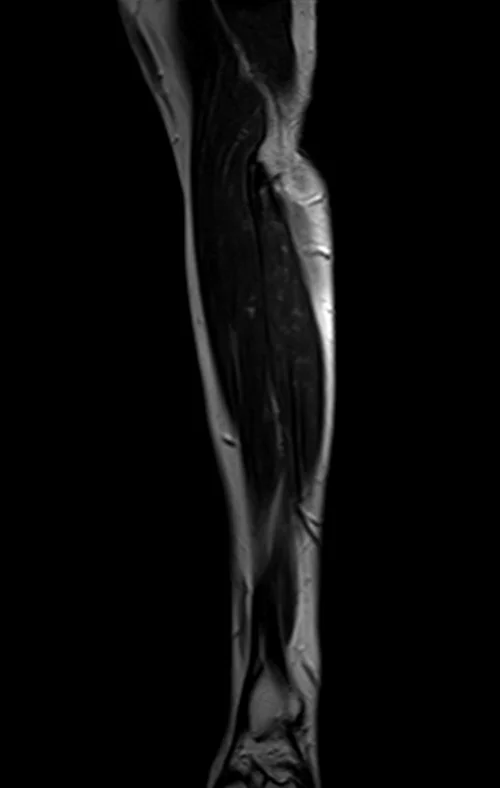

mri fore arm sagittal t2 image 3 - MRI